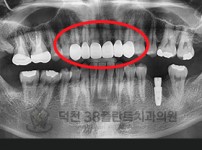

치료전후